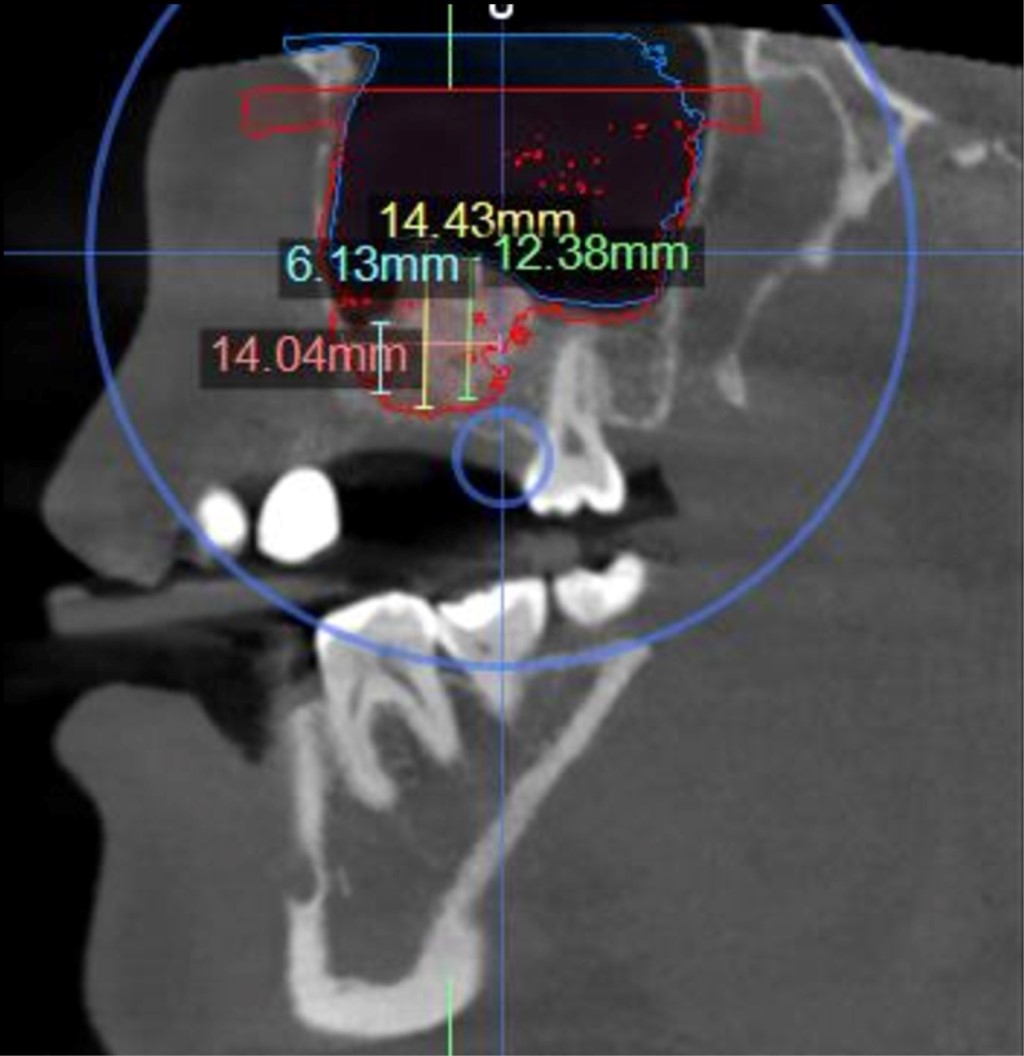

Figure 3